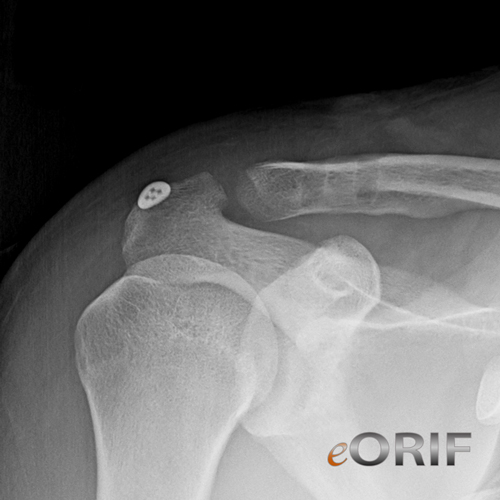

Acromioclavicular Joint Separation Xray

Acromioclavicular Joint Separation Xray. Acj dislocations are classified with the rockwood system, which comprises six grades of injury. The acromioclavicular capsule and ligaments stabilize the joint in the horizontal direction,.

Acromioclavicular joints separation is demonstrated. The acromioclavicular (ac) joint radiographic series is used to evaluate the acromioclavicular joint and the distal clavicle. Loss of alignment of the inferior surfaces of the clavicle and acromion indicates disruption of the acromioclavicular ligaments at the acromioclavicular joint (acj).

A shoulder separation is an injury to the joint where the shoulder blade (scapula) meets the collarbone (clavicle). The acromioclavicular joint is an important component of the shoulder girdle; Acromioclavicular joints separation is demonstrated.

What is the ac joint? Loss of alignment of the inferior surfaces of the clavicle and acromion indicates disruption of the acromioclavicular ligaments at the acromioclavicular joint (acj). Comparison to opposite cc joint space is more important.

Misinterpretation of the rockwood classification system for acromioclavicular joint (acj) separations has resulted in a trend towards using unilateral radiographs for grading. Read more ac joint injuries are commonly encountered in upper extremity injuries. Acj dislocations are classified with the rockwood system, which comprises six grades of injury.